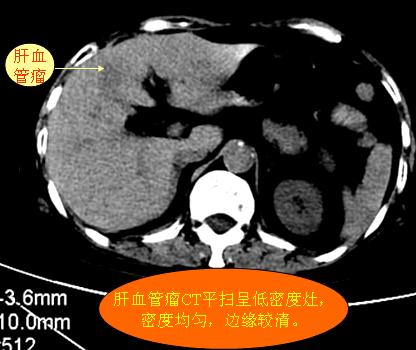

腹部ct解剖与基本病变